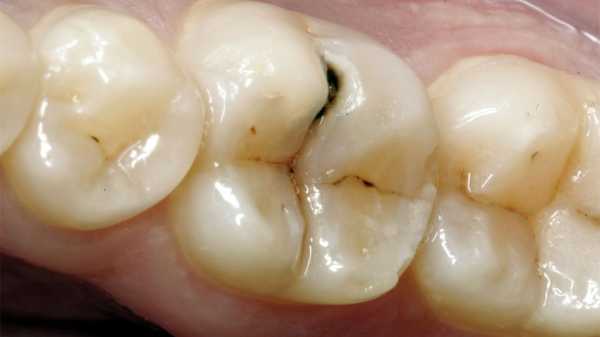

Кариес встречается почти у каждого человека. Проявляется в виде темных пятен на эмали. Интересно, что первоначальная стадия кариеса проявляется не темными, а белыми пятнами. В этих местах только начался патогенный процесс, и продукты жизнедеятельности бактерий понемногу разрушают минералы, которые делают зубную эмаль твердой. Постепенно микробы проникают все глубже, очаг становится крупнее в размерах. Болезнь может перекинуться на соседние элементы. Если кариес добрался до дентина, то процесс ускоряется, т.к. этот слой более мягкий и пористый. Если вовремя не вылечить кариес, то инфекция проникнет в пульпу – т.е. начнется процесс воспаления нервной и сосудистой ткани. Пульпит можно вылечить не «убивая» нерв, но не всегда. Обычно воспаленное содержимое пульпы и корневых каналов вычищается, обеззараживается и пломбируется.

Кариес зуба может вызывать боль

Болевые ощущения при кариесе и пульпите носят различный характер. Если при кариесе чувствуется не очень сильная боль, сопровождающаяся реакцией на горячие и холодные напитки, пищу и воздух. То боль при пульпите она зачастую очень сильная и внезапная (может заболеть ночью, что «хоть на стенку лезь»). Поврежденный элемент болезнен при надавливании и постукивании. Неприятные ощущения могут отдаваться в нос, щеки, виски (если поражен верхний зуб) и в шею, ухо (если воспаление находится в нижнем ряду).

При кариесе боль утихает, если убрать раздражитель. Например, поели сладкого, оно попало на зуб, тот разболелся. При пульпите же боль будет держаться очень долго.

- Кариес — поражение твердых тканей зуба патологически процессом – размягчение эмали и дентина, разделяют на поверхностный, средний, глубокий и кариес стадии пятна. В зависимости от степени поражения эмали симптомы то же разные. Учитывая, что болевая чувствительность у всех людей не одинаковая, а современные зубные пасты уменьшают болевые ощущения, в большинстве случаев симптомы кариеса сглажены. При кариесе боли кратковременные от нескольких секунд до 15-20 минут, боли могут быть от холодного/горячего, сладкого/кислого и при попадании пищи в кариозную полость, боль проходит после устранения раздражителя.